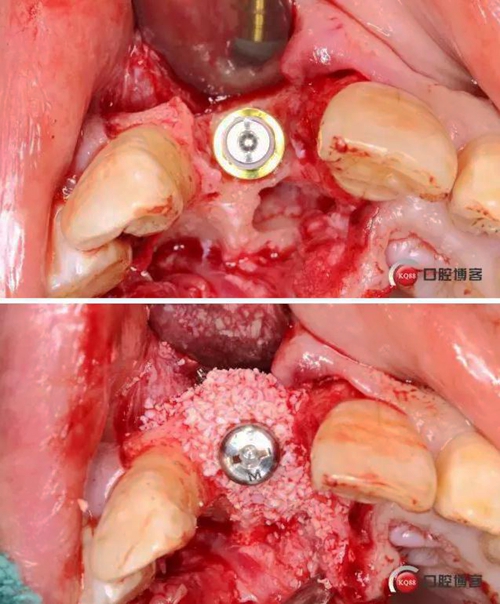

術(shù)中照